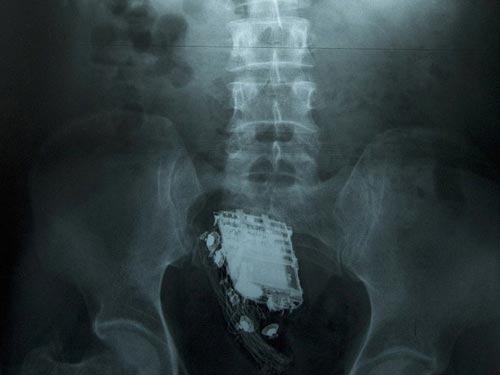

Gã tù nhân 58 tuổi bị ban quản lý nhà tù Welikada (Kotte, Sri Lanka) đưa đến bệnh viện cấp kỳ. Kết quả chụp X-quang phơi bày chiếc điện thoại đang ngự trong bụng ông ta và các bác sĩ phải giải phẫu lấy ra.

Chiếc điện thoại trú ngụ trong ruột tù nhân. Ảnh: Daily Mail